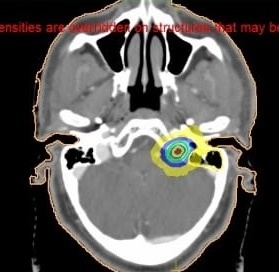

Cavernous sinus meningioma treated with SRS by Manishi Bansal | Nov 27, 2021 | Uncategorized A patient presented with ptosis and diplopia. On investigation found to have cavernous sinus meningioma. Treatment done with single fraction radiation (SRS) . After one month ptosis and diplopia improved significantly.